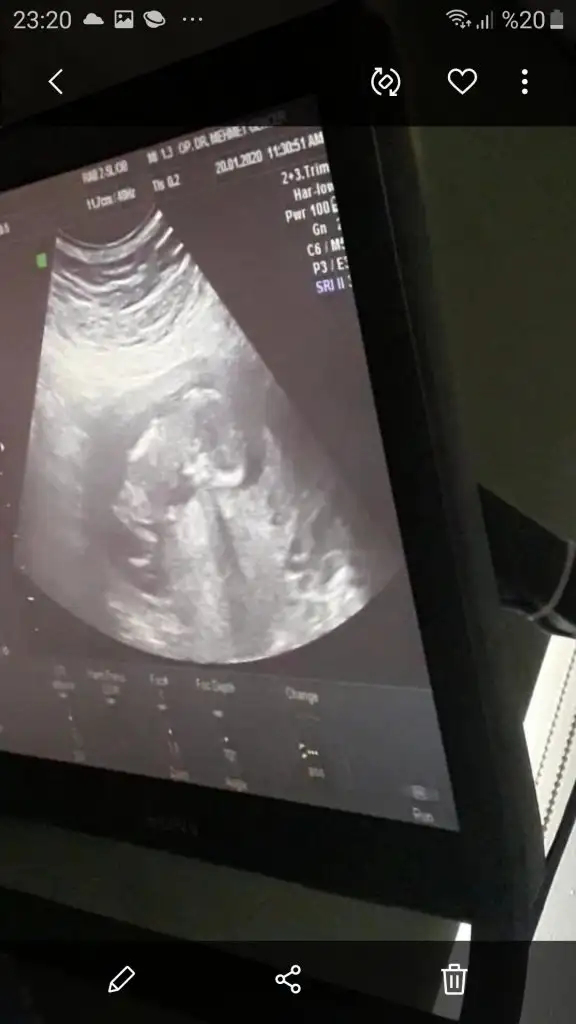

dr soylemeden siz gorun genital nub teorisi ( bebegin cinsiyeti)

Merhabaa 6+3 karından ultrasonumm cinsiyet tahminii yapabilirmisiiniz🥰

valla hepsini çektim bu son seni sıkmıcam kusıra bakma son kez bak 😂😂 eşimde soruyo durmadan☺